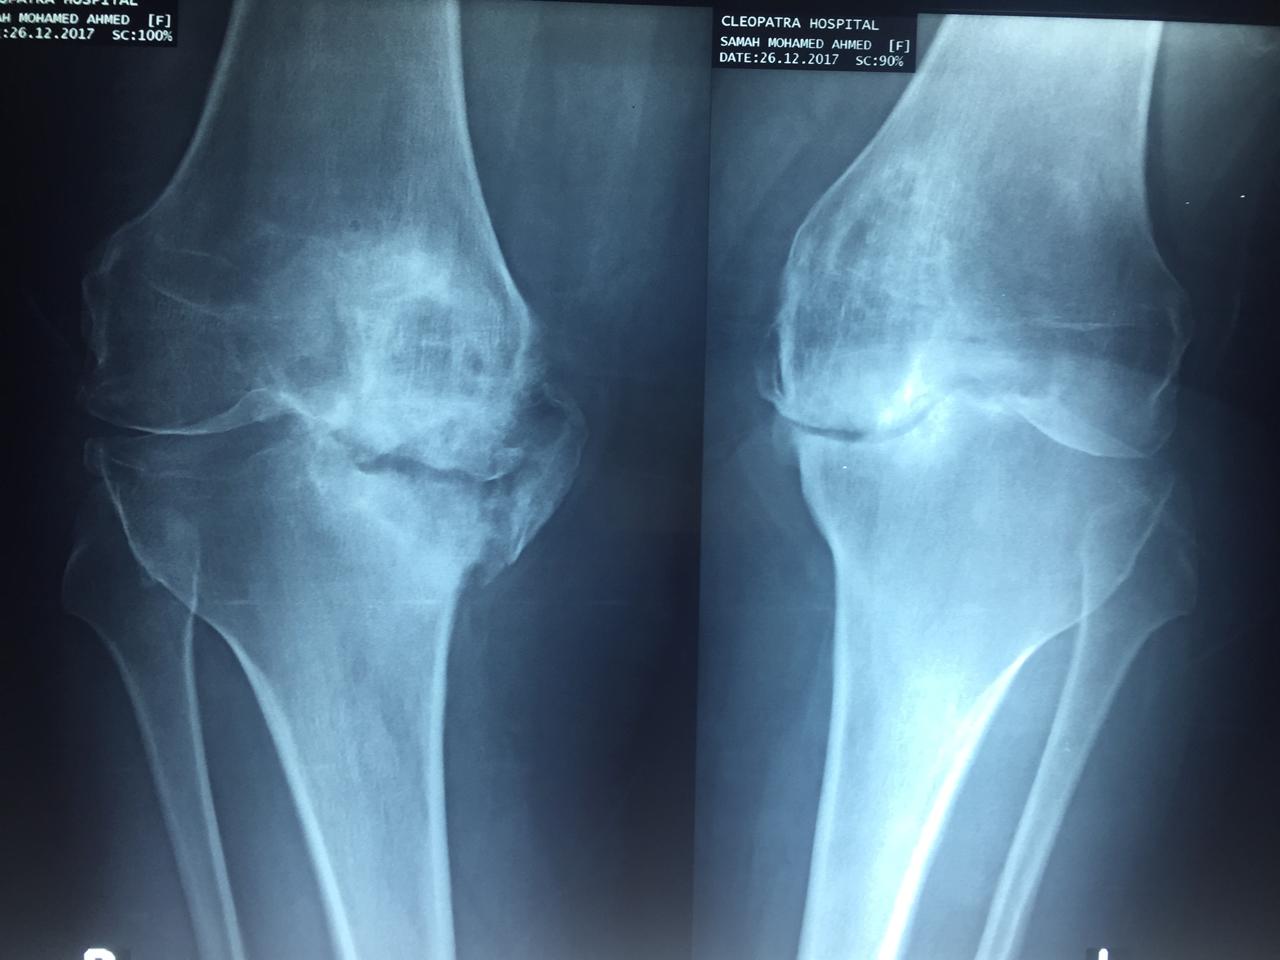

صوره لتاكل شديد جدا بالركبة مع وجود نقص شديد بالجزء الداخلي لأعلى عظمة الساق.